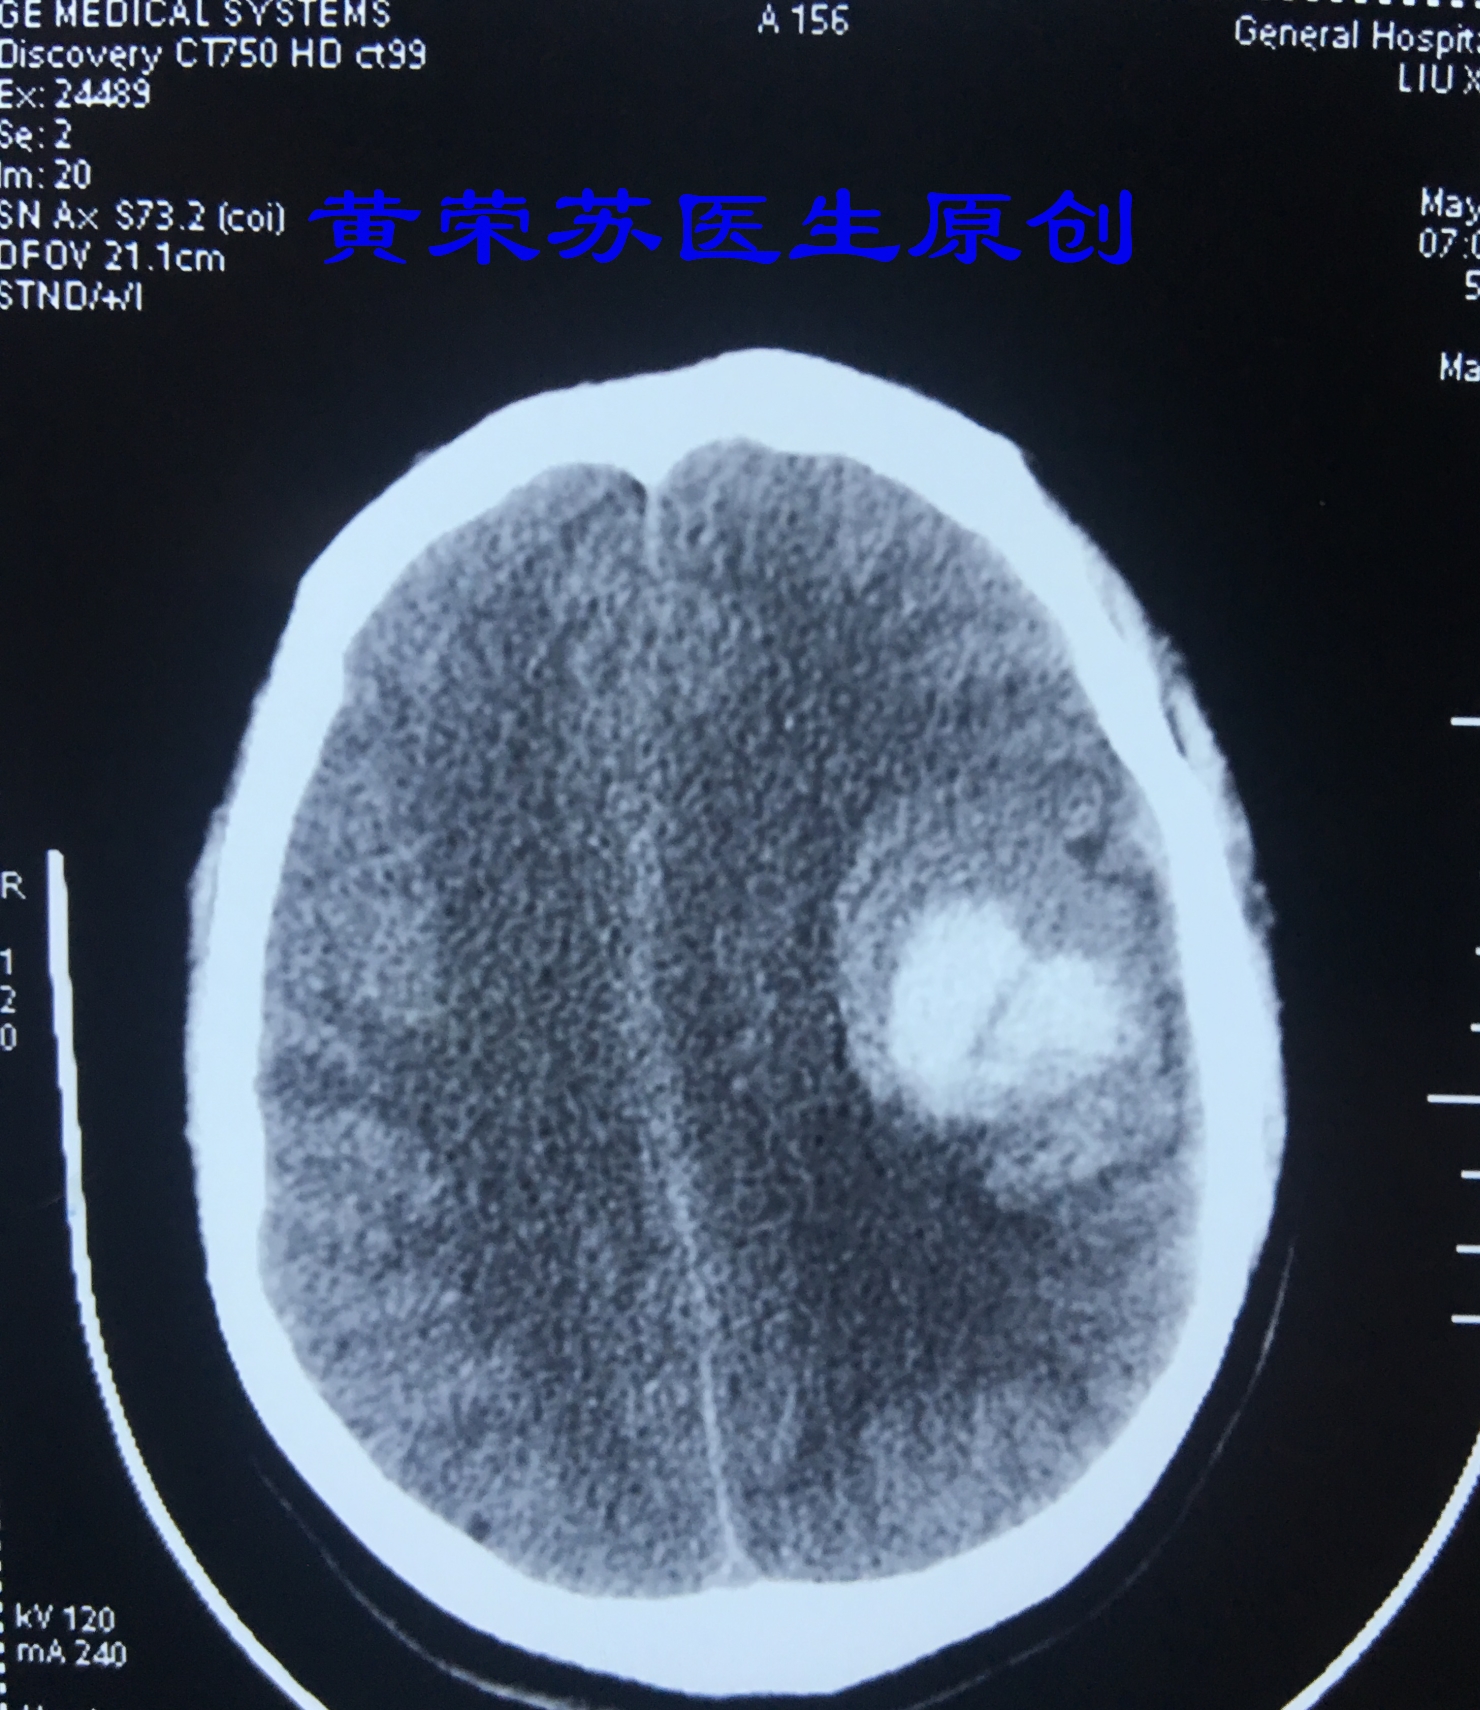

1、最常见的部位:基底节区脑出血,占60%~70%,该部位出血常出现三偏征(病灶对侧偏瘫、偏身感觉障碍、偏盲)。壳核和丘脑是高血压脑出血最常见的部位。

图一、典型的基底节区脑出血,破入脑室,形成脑室系统铸型